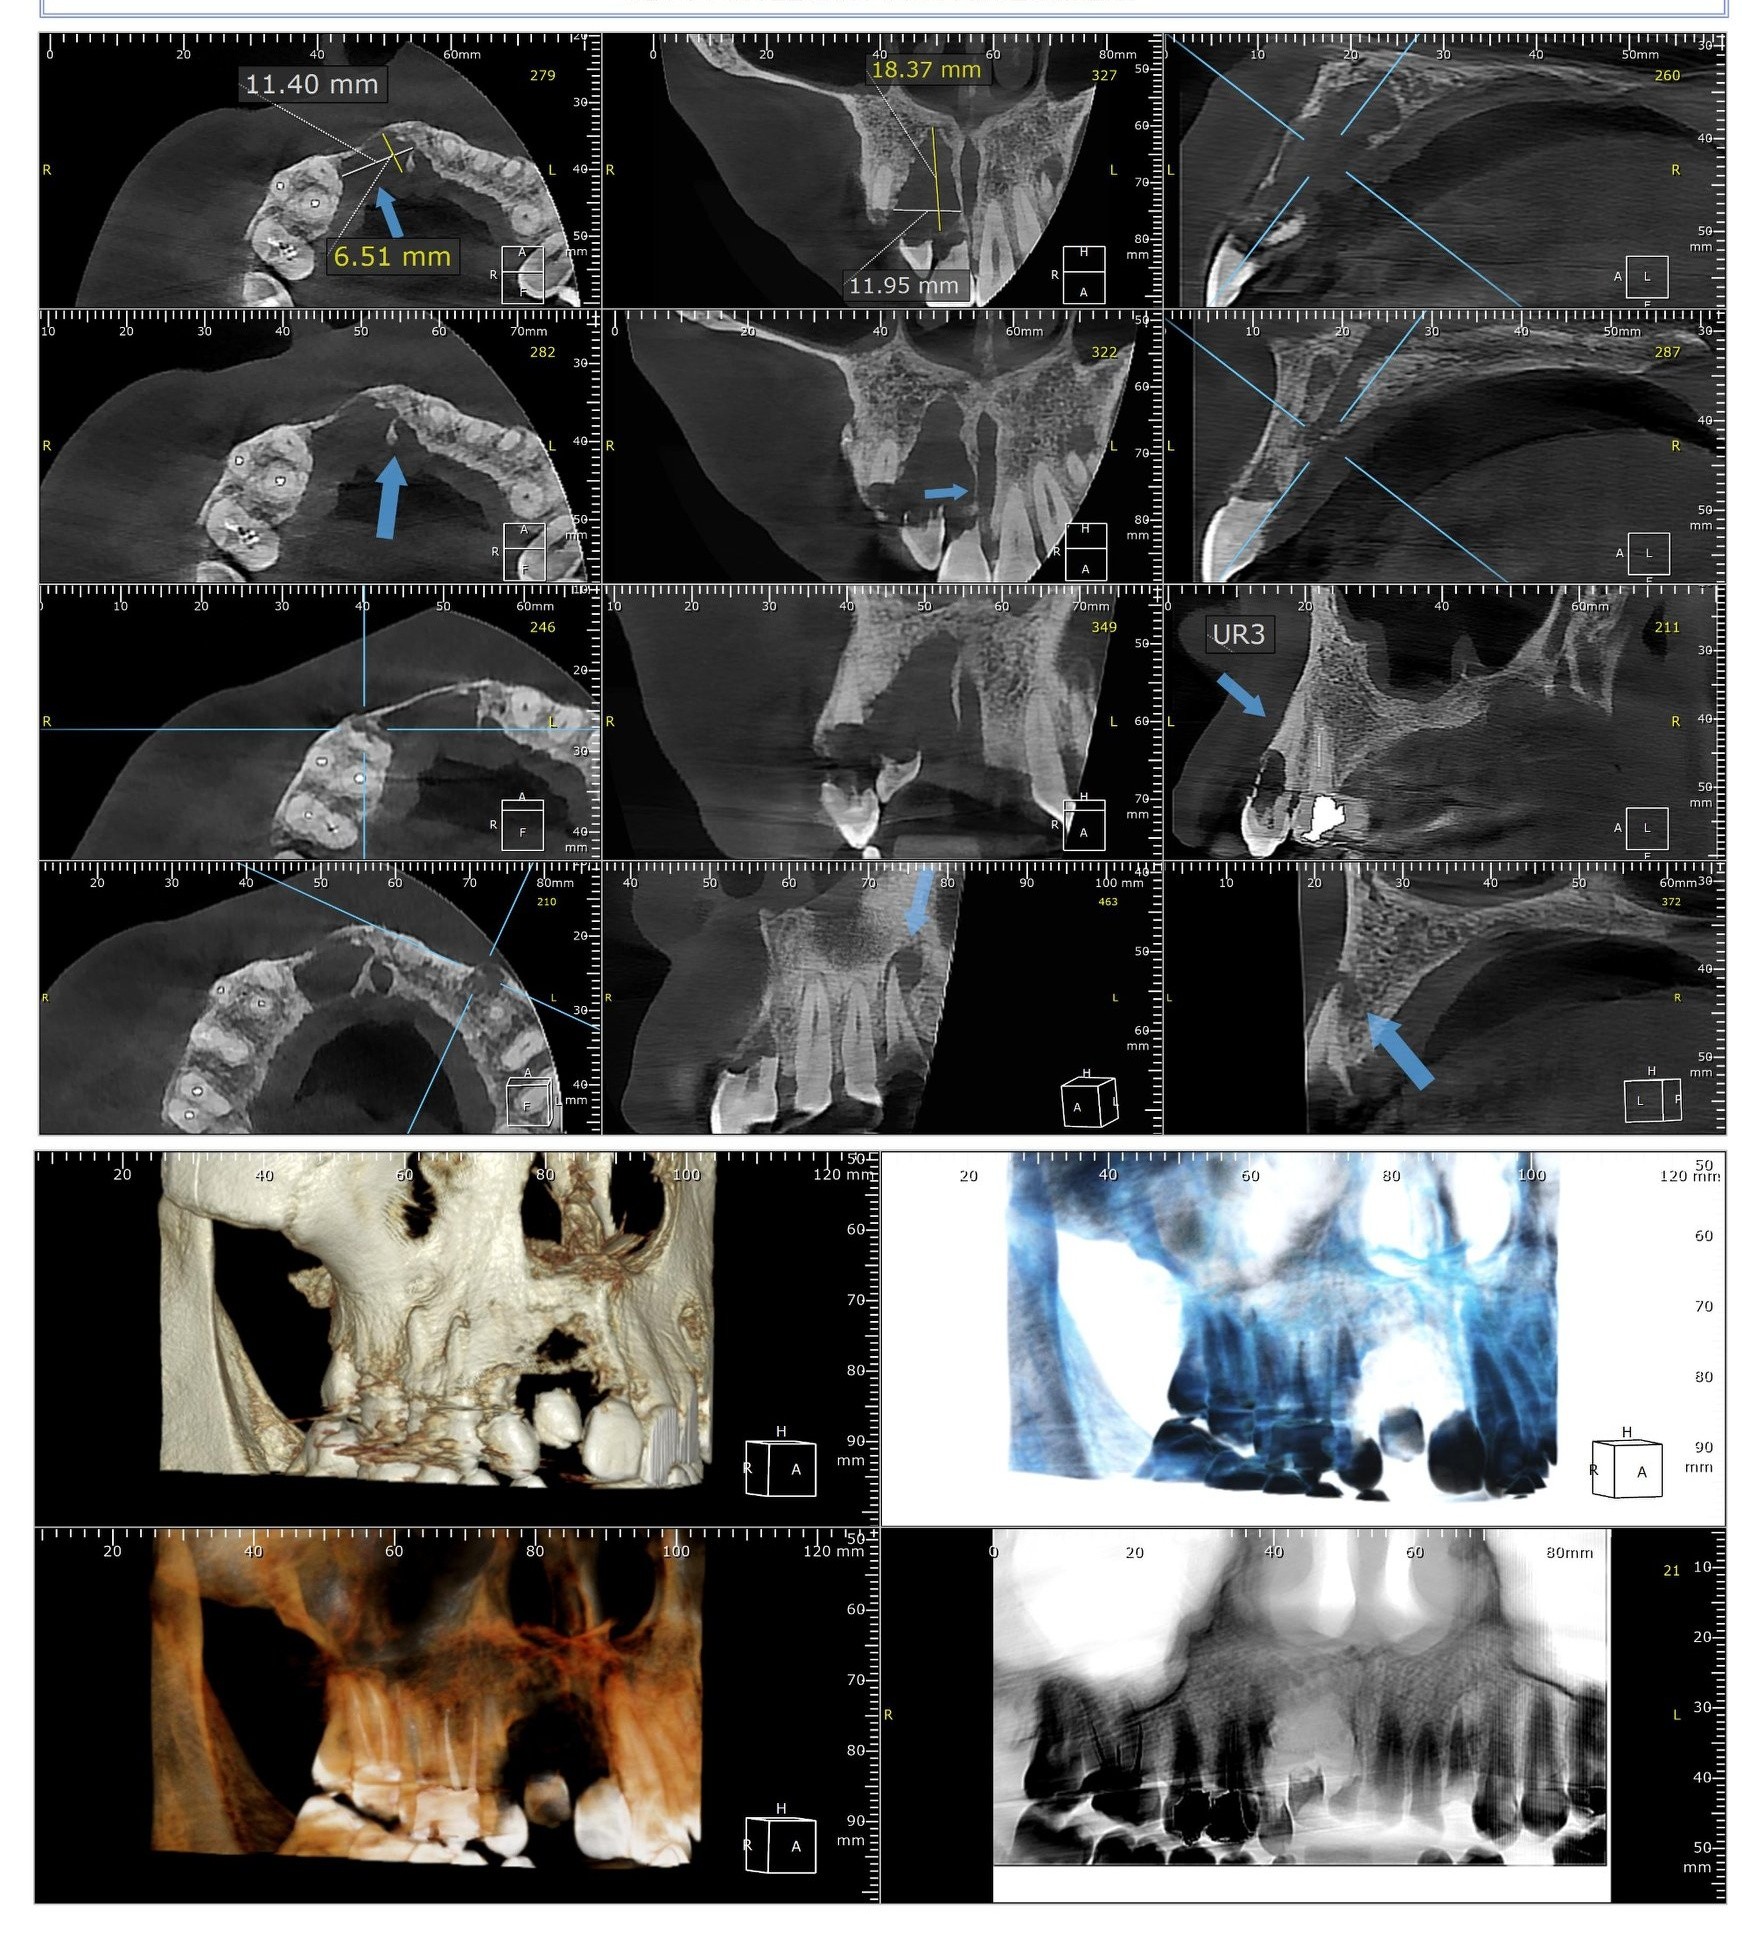

بتوجيهات الدكتور عمرو دويدار، وكيل وزارة الصحة بسوهاج، وفي إطار حرص المديرية على تعزيز الخدمات الطبية المقدمة للمواطنين بكافة التخصصات، نجح فريق جراحة الفم والأسنان بمستشفى سوهاج العام في إجراء عملية جراحية دقيقة لاستئصال ورم بالفك العلوي لمريضة في العقد الخامس من العمر.